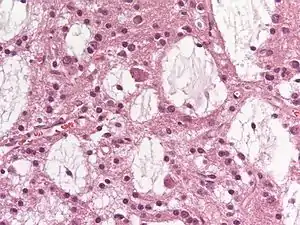

a-d)Ultrastructural findings of dysembryoplastic neuroepithelial tumors

Dysembryoplastic neuroepithelial tumours are largely glioneuronal tumours, meaning they are composed of both glial cells and neurons.[2]

Three subunits of DNTs have been commonly identified:[2]

- Simple: Specific glioneuronal elements are the sole components of simple DNTs.[2]

- Complex: Glial nodules and/or type 3b focal cortical dysplasia (FCD), in addition to the glioneuronal elements are present in complex DNTs.[4] Both the nodules and FCD can be present within the same tumour, though only 47% of complex DNTs are linked to FCD.[2]

- Nonspecific: Nonspecific DNTs are lacking the glioneuronal elements common to DNTs but will show glial nodules and/or type 3b FCD.[2] Eighty-five percent of nonspecific case of DNTs show this FCD.[2]

There currently exists some debate over where to make the proper division for the subunits of DNTs. A fourth subunit is sometimes noted as a mixed subunit. This mixed subunit expresses the glial nodules and components of ganglioglioma.[1] Other findings suggest that DNTs require a reclassification to associate them with oligodendrogliomas, tumours that arise from solely glial cells.[3] These reports suggest that the neurons found within DNTs are much rarer than previously reported. For the neurons that are seen in the tumours, it is suggested that they had been trapped within the tumor upon formation, and are not a part of the tumour itself.[3]